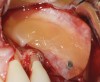

Fig 11. Schneiderian membrane perforation covered with a PRF membrane.

Figure 11